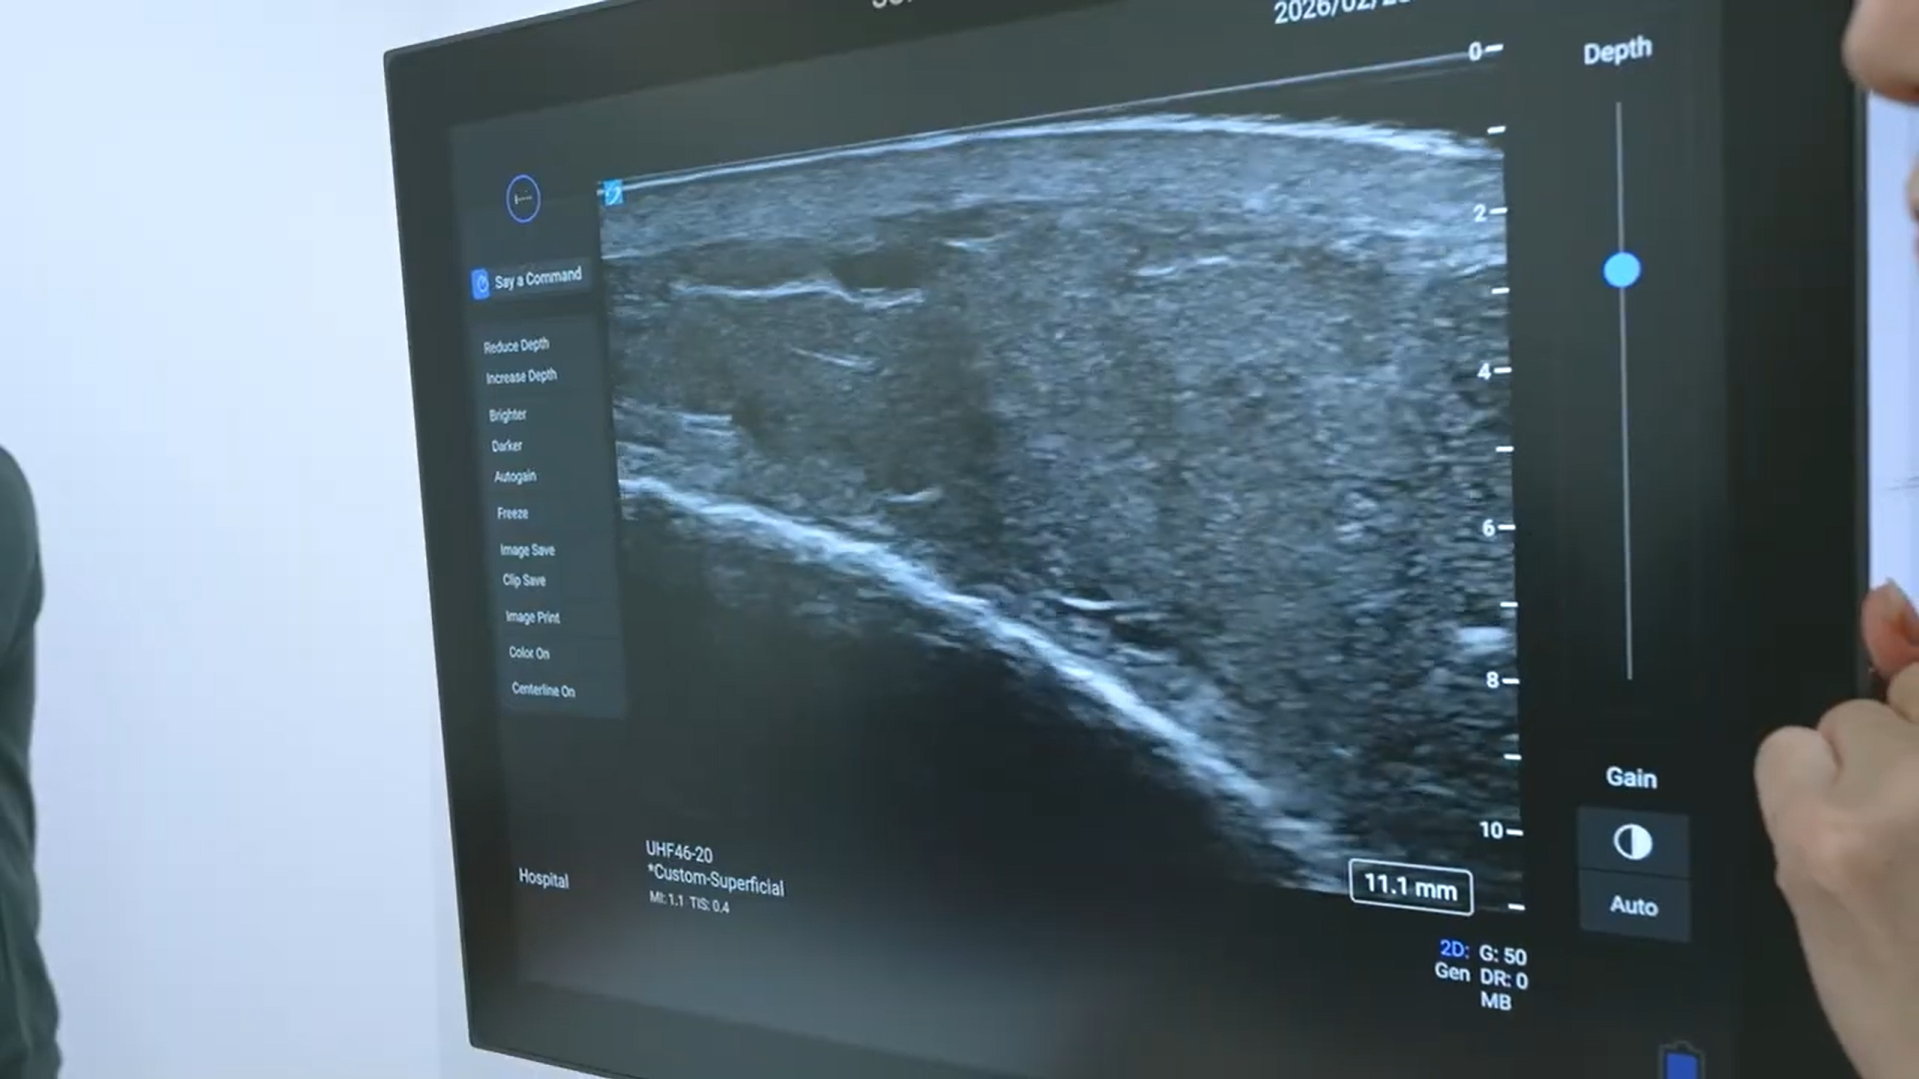

そこで導入されたのが、超高周波によりリンパ管や微細血管を高精細に描出する「Sonosite LX(ソノサイト エルエックス)」です。本機は、従来より高い周波数帯域を用いることで浅層から深部までを高精細に描出できる超音波画像診断装置です。皮下のリンパ管や微細血管といった極めて細い構造を鮮明に可視化します。音声操作機能を備え、画像の静止や条件調整をハンズフリーで行うことが可能です。

説明会では、片脚にリンパ浮腫を抱える患者さんの協力を得て実機デモンストレーションが行われました。まず浮腫のある脚にプローブを当てると、モニター上に血管構造が映し出されました。永尾院長は画面を指し示しながら、静脈とリンパ管の位置を明確に説明します。

リンパ浮腫の足のエコー映像

「ここに静脈があります。そして、この細い走行がリンパ管です」

続いて健常な側の脚にもプローブを当てると、浮腫のある側とは異なる構造が描出されました。リンパ管の走行や周囲組織の状態の違いが視覚的に確認され、左右差が明確に示されました。

デモの最中、永尾院長は両手をプローブに添えたまま音声で指示を出します。

「Freeze」→ 画像が瞬時に静止します。

「Color」→ 血流がカラー表示に切り替わります。

「Gain up」→ 明るさが調整され、構造がさらに鮮明になります。

操作のたびに手を離す必要はありません。声だけで画像が止まり、カラー表示に変わり、条件が調整されます。診断の流れを途切れさせることなく、画面上の情報が整理されていきます。視覚情報をその場で確認し位置を示すという一連の過程は、熟練医の経験値に可視化という確信が重なり、診療の判断をより明確にしていく様子を示していました。